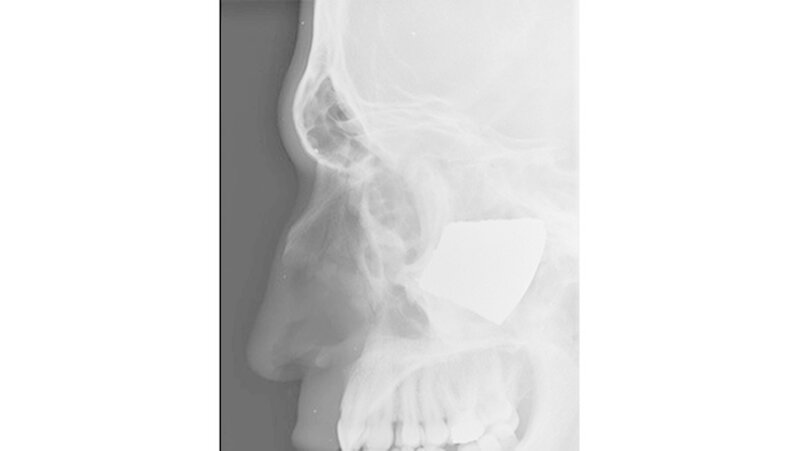

Vom Bohrer im Kopf bis zum Schlüssel in der Kieferhöhle: Die MKG-Chirurgen der Charité haben ausgewählte Patientenfälle mit Fremdkörpern im Gesicht zusammengestellt. In unserer Fotostrecke finden Sie die eindrucksvollen Aufnahmen.